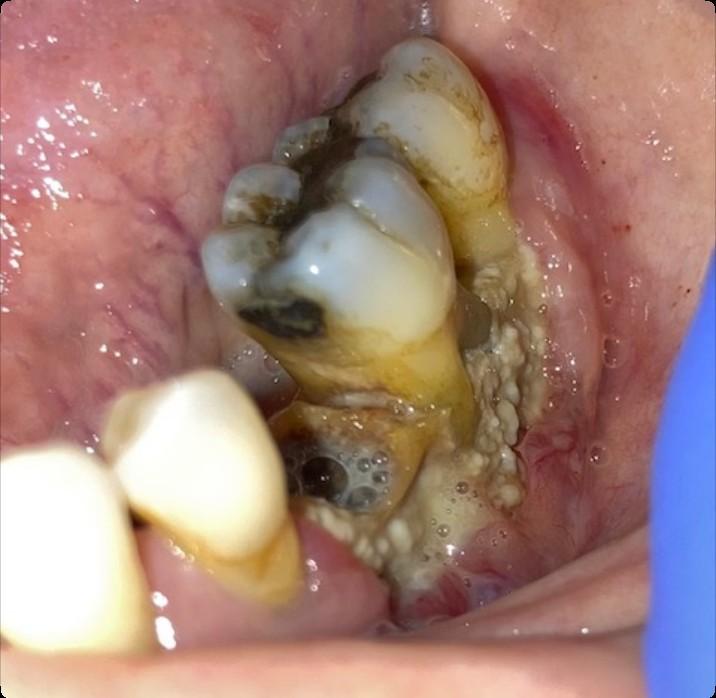

Osteonecrosis of the Jaw

MRONJ: Medication Related Osteonecrosis of the Jaw

• Rare oral side effect called osteonecrosis of the jaw that is associated with certain medications, bone-modifying agents.

• Osteonecrosis of the jaw is a condition where small area(s) of the jawbone have difficulty healing and the bone starts to breakdown and die.

How Common is MRONJ?

The risk is thought to be less than 1% for patients taking IV bonemodifying agents, and at least ten times less likely than that for patients taking the drugs by mouth.

If I take these medications, am I automatically at risk?

• Anyone who takes these medications has a chance of developing ONJ.

• However, most reported cases occur after a type of oral “injury” – which could a tooth extraction, chronic periodontal (gum) disease, an oral surgical procedure, or simply a nonhealing traumatic ulceration.

• Tobacco use, treatment with corticosteroids, long-term use of bonemodifying agents, and diabetes also may increase the risk of this condition occurring.

What are the signs of MRONJ?

• The hallmarks of ONJ are exposed bone or gum/mucosa/tissue wounds that heal very slowly or do not heal at all for eight weeks or more after an injury to the mouth.

• Some patients report that this begins with a feeling of “roughness” on the gum tissue. If these open wounds become infected, there may be pus or swelling in the adjacent gum tissue.

• Many times, this condition is painless in the beginning, and patients only experience pain after the exposed bone becomes infected.

How is MRONJ treated?

• Education

• Careful oral hygiene

• Conservative interventions

• Avoid surgical intervention, if possible

• PATIENCE!